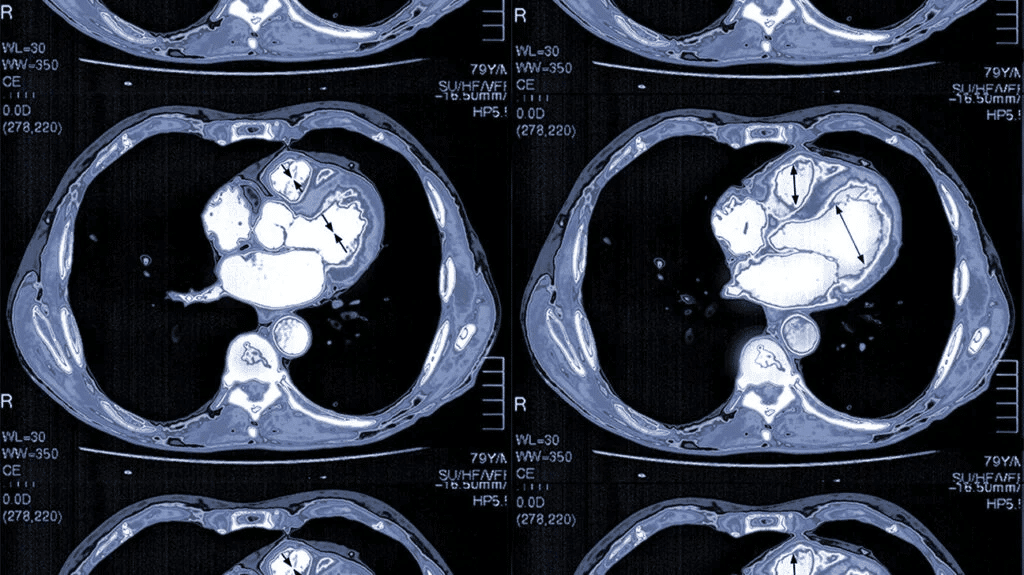

سی تی آنژیوگرافی عروق کرونر یک روش تصویربرداری غیرتهاجمی و پیشرفته از عروق قلب است که با استفاده از اشعه ایکس و ماده حاجب حاوی ید، تصاویر سه بعدی دقیق از شریانهای کرونر ایجاد می کند. این روش به پزشکان کمک می کند تنگیها، انسدادها و پلاکهای چربی یا کلسیم در عروق قلب را شناسایی کنند.

- ریتم قلب نامنظم شدید: آریتمی های شدید باعث تاری تصاویر و کاهش دقت تشخیص

- محدودیت در بیماران خاص: افرادی با وزن بالا یا ضربان قلب نامنظم ممکن است تصاویر با کیفیت مطلوب ثبت نشود.

مطالعات اخیر نشان میدهند که حدود ۹۵٪ از تصاویر سی تی آنژیوگرافی عروق کرونر کیفیت کافی برای تشخیص دقیق تنگیها و انسدادها را دارند. همچنین طبق گزارش انجمن قلب آمریکا (AHA)، استفاده از CCTA میتواند ریسک سکته قلبی را در بیماران با ریسک متوسط تا بالا تا ۳۰٪ کاهش دهد، چرا که تشخیص زودهنگام انسدادها و پلاکهای کرونری ممکن میشود.